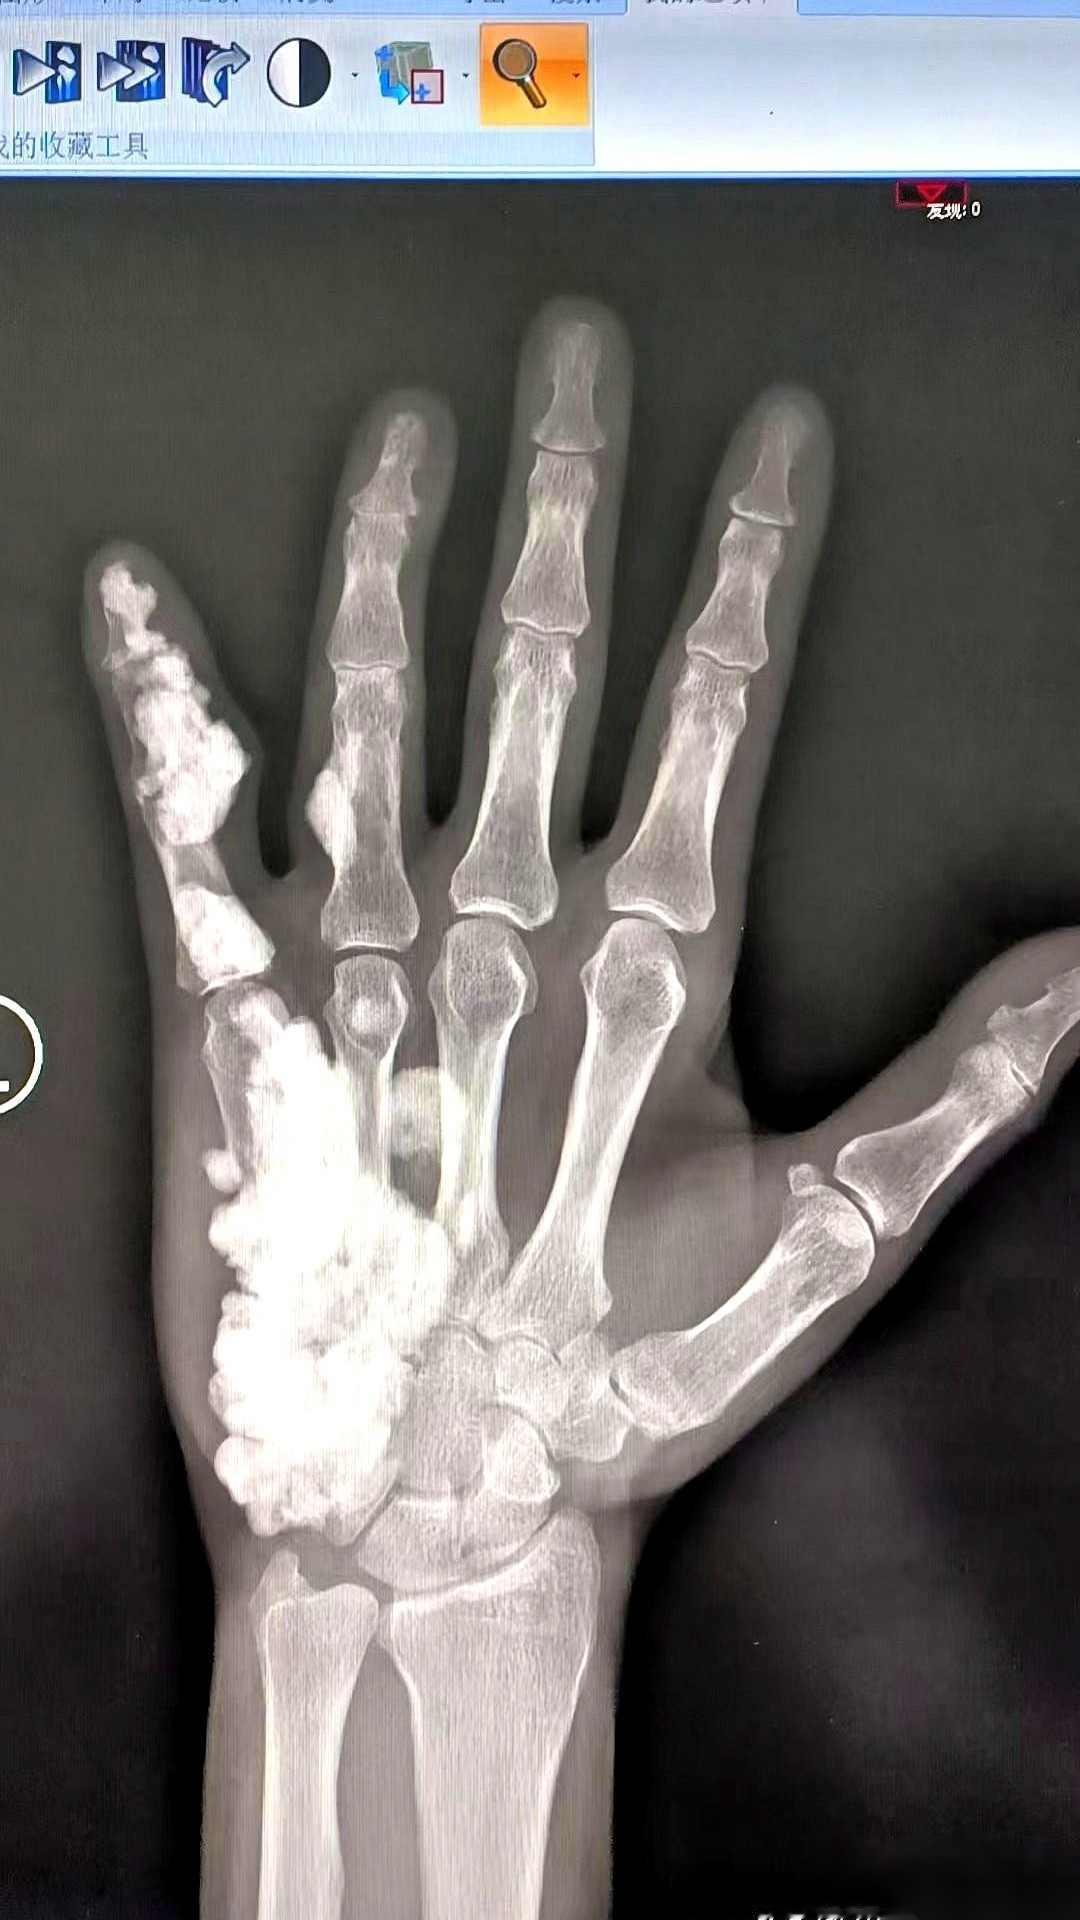

17岁,左手疼了整整10年。拍了个片子,我人都看傻了。 医生把X光片递过来,我盯着那团歪歪扭扭的影子看了好一会儿,左手小指的骨头像是被什么东西烫过,表面一层层皱起来,像蜡油滴下来又凝住,这根手指从二年级开始就时不时疼,我一直以为是长歪了,原来它里面藏了这么个东西。 这哪是骨头啊,整个一抽象艺术品!X光片里小指骨跟老树根似的,疙疙瘩瘩还带分叉。医生说这叫"骨软骨瘤",听着挺唬人,其实就是骨头长劈叉了——本来该直溜长的骨头,非要在旁边瞎发芽。 想想真憋屈。七年里写字握笔别扭,打球不敢接传,连握女朋友手都得换右手。合着天天揣着个"骨刺"当宝贝,还以为是小时候摔跤落下的毛病。现在看片子上那坨增生骨头,活像外星生物寄生。 医生说这玩意得手术锯掉,听得我后槽牙发酸。想想电锯磨骨头的声儿,晚上做梦都能吓醒。不过要是不处理,以后可能越长越大,到时候真成"九指神丐"了。 最亏的是耽误这么多年。要是早发现早治疗,现在弹吉他玩键盘早溜熟了。我们校篮球队长当初还笑我投篮姿势怪,哪知道是骨头里藏了"违章建筑"。 医院让下周动手术,说是微创刮除就行。就是术后得戴三个月支架,估计得被哥们笑成"钢铁侠"。不过能甩掉这缠了十年的老伙计,值了! 各位读者你们怎么看?欢迎在评论区讨论。手指受伤 手指离断伤 手指手掌麻木 手和胳膊疼 手指很疼 手指骨头疼